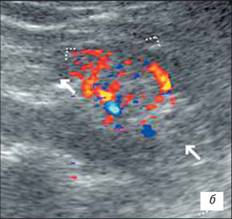

УЗІ нирки при запальних змінах в режимі ЦДК

а – інтраренальний судинний малюнок нирки збережений, кортикальный кровотік визначається у всіх відділах паренхіми;

б – збіднення судинного малюнка;

в – швидкісні показники в гирлі ниркової артерії в межах вікової норми: Vps– 83,7 см/с; Ved– 34,1 см/с; RI– 0,63; PI– 0,96.

На розгорненій картині УЗІ з ЦДК характеризується нерівністю, нечіткістю, деформацією контура нирки, який місцями може не простежуватися; нирка іноді місцями погано диференціюється від навколишніх тканин, що утрудняє визначення її розмірів; візуалізуються дрібні, неправильної форми втягнення контура, розподілені або по всьому контуру, або в якомусь фрагменті нирки; визначається нечіткість кортико-медуллярной диференціювання; є виражені дифузні зміни паренхіми нирки з помірним нерівномірним підвищенням її эхогенності; дилатація чашечно-мискової системи; фрагментарне стоншування паренхіми нирки з компенсаторним потовщенням або збереженням товщини інших її ділянок помірне збіднення інтраренального судинного малюнка, найбільш виражене в місцях деформації і втягнення контура нирки; зниження швидкісних характеристик артеріального кровотоку (мал. 3).